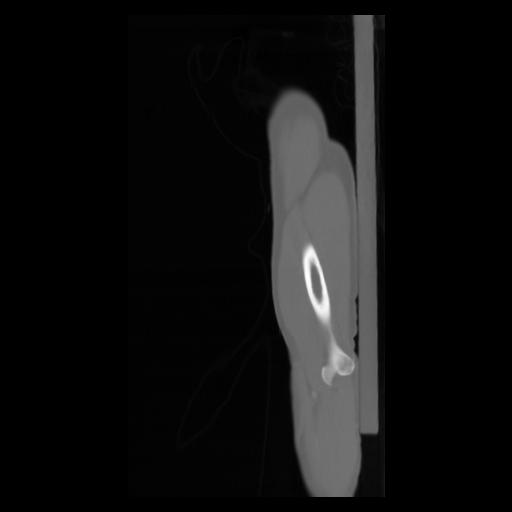

30 CUERPO,CE,Sagittal,3.000,CUERPO,Sagittal,